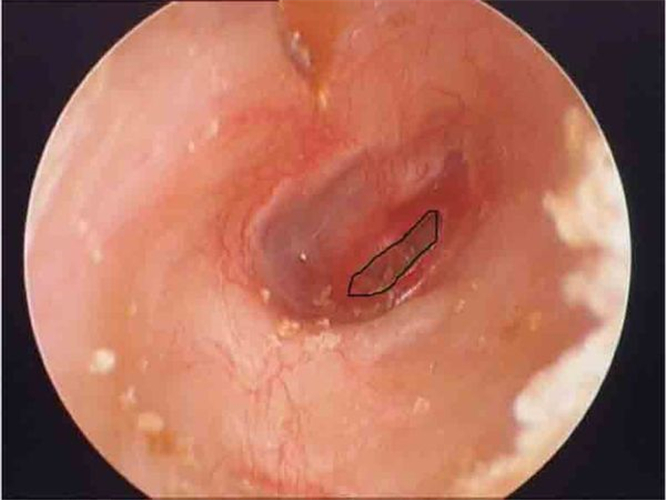

治好的鼓膜穿孔